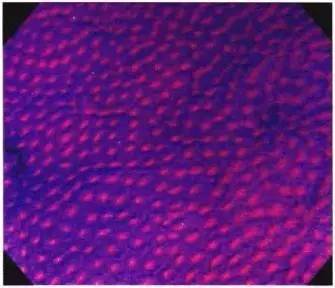

图4a:I型pit:圆形pit。

正常组织中,从凹陷表面观察通常为圆形pit。

图4b:II型pit:星芒状pit。

粘膜组织增生后,病理学上pit pattern会形成锯齿状改变,从水平断面观察可看到类似星星一样的星芒状。